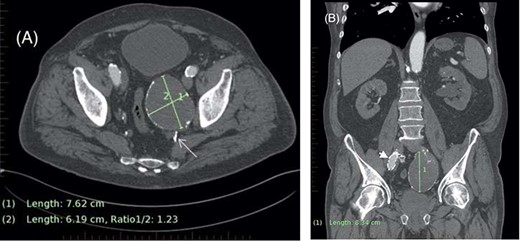

After relocating to the catchment area of our hospital, he presented in acute urinary retention. A CT kidney, ureters and bladder (CTKUB) demonstrated left hydronephrosis and hydroureter secondary to extrinsic compression from the enlarged left IIAA (from 58 mm to 76 mm in diameter) (Fig. 1A and B). Embolization was delayed by the associated acute kidney injury, which was first managed by the urologists with J-J stent insertion for ureteric decompression. He then entered a period of repeated urological interventions due to complications from his ureteric instrumentation, including urosepsis requiring a prolonged intensive care unit admission. When his urinary tract infections had cleared, a CTA demonstrated the IIAA to have further increased (83 mm × 71 mm), prompting urgent embolization (Fig. 2).

(A) Axial CT demonstrating left internal iliac aneurysm (IIAA) measuring ×76 62 mm with retrograde flow into the aneurysm (arrow) from the deep pelvic vessels. (B) Coronal CT demonstrating the left IIA with a craniocaudal length of 83 mm. The right external iliac artery endograft limb is also visible (arrowhead).